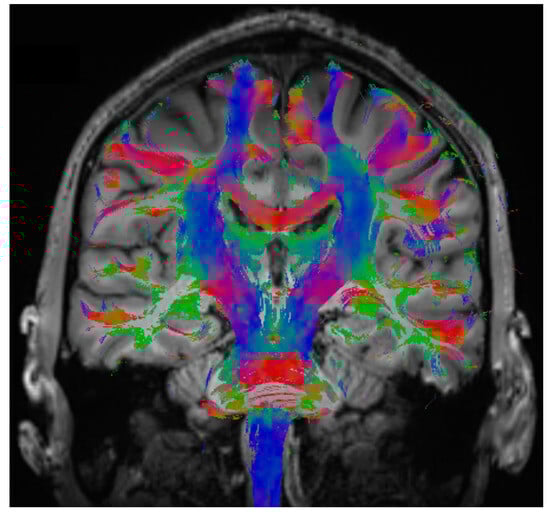

2.7. MR-Imaging

3.5. Analysis of MR-Imaging